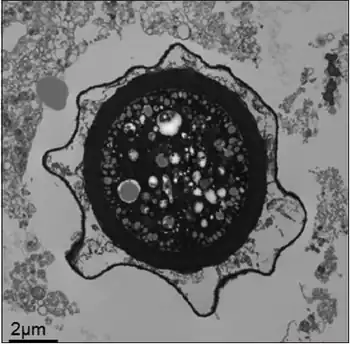

Transmission electron micrograph of a Balamuthia mandrillaris cyst

Balamuthia's lifecycle, like the Acanthamoeba, consists of a cystic stage and a non-flagellated trophozoite stage, both of which are infectious, and both of which can be identified in the brain tissue on microscopic examination of brain biopsies performed on infected individuals. The trophozoite is pleomorphic and uninucleated, but binucleated forms are occasionally seen. Cysts are also uninucleated, possessing three walls: an outer thin irregular ectocyst, an inner thick endocyst, and a middle amorphous fibrillar mesocyst.[9]